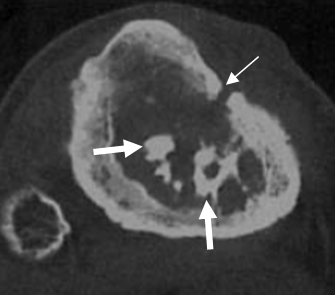

Fig 43 A. Osteomielitis crónica.

TAC axial. Engrosamiento de la cortical en la tibia y defecto óseo en la parte anterolateral, por trayecto fistuloso. (Flecha delgada). En el interior de la medula osea se encuentran fragmentos densos y espiculados, que corresponden a secuestros. (Flechas gruesas).